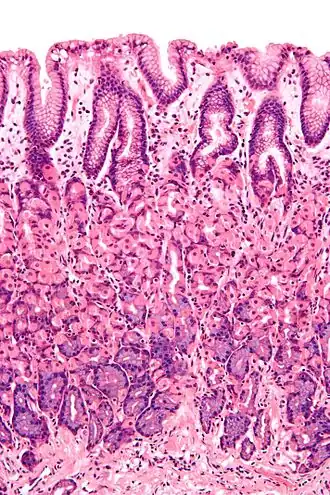

Simple columnar epithelium is a single layer of columnar epithelial cells which are tall and slender with oval-shaped nuclei located in the basal region, attached to the basement membrane. In humans, simple columnar epithelium lines most organs of the digestive tract including the stomach, and intestines. Simple columnar epithelium also lines the uterus.

Simple columnar epithelium is further divided into two categories: ciliated and non-ciliated (glandular). The ciliated part of the simple columnar epithelium has tiny hairs which help move mucus and other substances up the respiratory tract.

The shape of the simple columnar epithelium cells are tall and narrow giving a column like appearance. the apical surfaces of the tissue face the lumen of organs while the basal side faces the basement membrane.[1] The nuclei are located closer along the basal side of the cell.[1]

Absorptive columnar epithelium is characterized as having a striated border on its apical side, this border is made up of non-motile microvilli allowing for increase surface area for absorption.[1] These are known as non-ciliated columnar epithelium. Non-ciliated simple columnar epithelium is made up of glandular goblet cells which secrete mucin to form mucus.[1] The rest of the cell is made up of cytoplasm with membrane bound secretory granules which secrete the mucin, and are found towards the apical surface of the cell.[1]

These are found in the lining sections of the gastrointestinal tract (inner lining of oesophagus, stomach, etc.) and may be brush bordered.

Vertical section of a villus from the dog's small intestine. X 80. (Simple columnar epithelium labelled at right, third from the top.)

Transverse section of a villus, from the human intestine. X 350.

a. Basement membrane, here somewhat shrunken away from the epithelium.

b. Lacteal.

c. Columnar epithelium.

d. Its striated border.

e. Goblet cells.

f. Leucocytes in epithelium.

f’. Leucocytes below epithelium.

g. Blood vessels.

h. Muscle cells cut across.